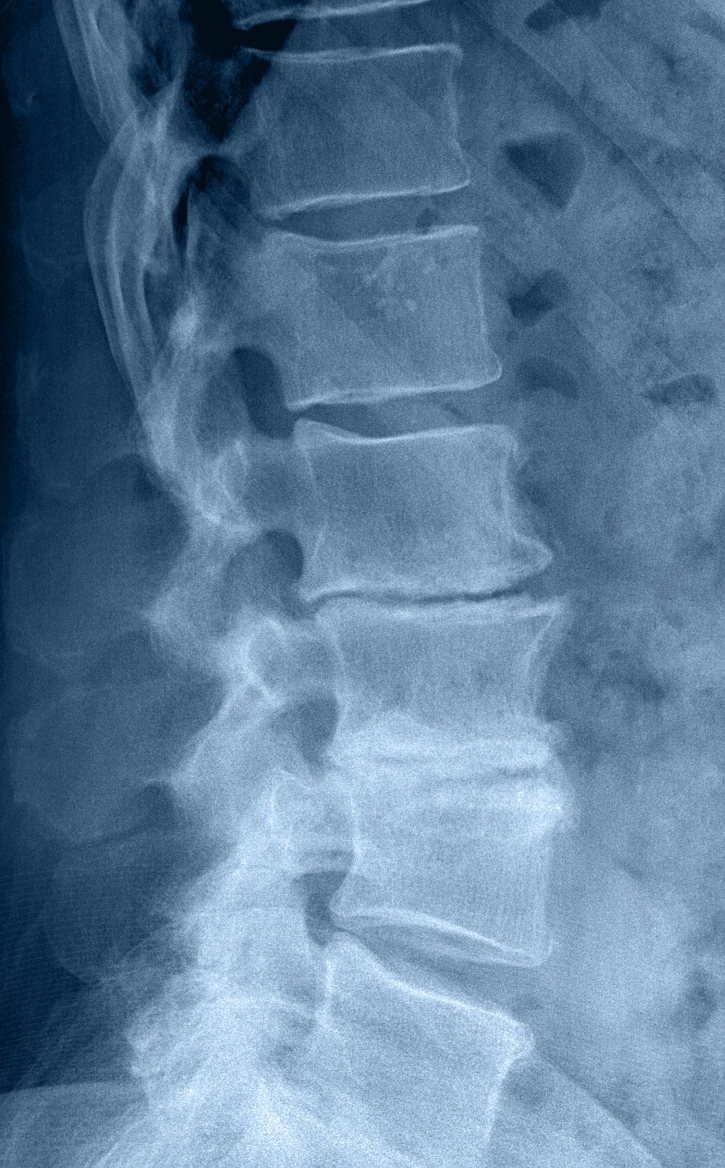

Degenerative Disc Disease (DDD)

What is it?

Occurs when spinal discs lose hydration and elasticity over time, reducing their ability to absorb impact and support smooth motion.

How it Happens?

Most commonly age-related disc changes, sometimes accelerated by repetitive strain, posture, smoking, genetics, or prior injury.

Symptoms

Chronic neck or low back pain, stiffness, and sometimes radiating pain into arms or legs—often worse with sitting, bending, or twisting.

Spinal Stenosis

Spinal stenosis is narrowing inside the spine that compresses nerves or the spinal cord (lumbar or cervical).

Age-related changes like disc shrinkage, thickened ligaments, and bone spurs; sometimes arthritis or prior injury.

Back/neck pain, numbness/tingling/weakness, and leg heaviness or cramping with walking/standing (neurogenic claudication).